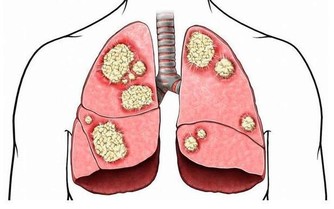

我們都說“胃是喇叭,肝是啞巴”,是因為:胃痛你有感覺,但沒有人會說肝疼。

因為肝臟是唯一沒有痛感神經的器官,這樣人們經常忽略它健康狀況的原因。

因肝臟視人體最大的排毒器官,所以:肝不好,未老先倒;肝淨,皮膚都嬌嫩!

一、肝臟毒素堆積的表現